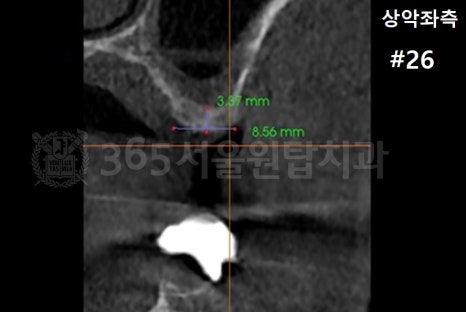

염창동 임플란트 식립 각도는 3차원 CT를 충분히 활용하여 확인하세요

염창역 임플란트 CT 설명을 위한 예시 자료입니다.

3D CT를 통해

뼈의 두께와 밀도, 신경 위치를 확인하고

최종 보철물의 형태까지 예측합니다.